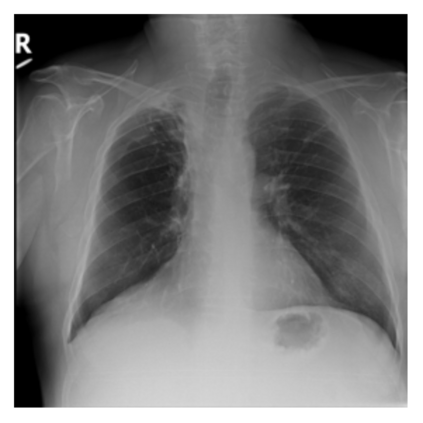

The evaluation of infectious disease processes on radiologic images is an important and challenging task in medical image analysis. Pulmonary infections can often be best imaged and evaluated through computed tomography (CT) scans, which are often not available in low-resource environments and difficult to obtain for critically ill patients. On the other hand, X-ray, a different type of imaging procedure, is inexpensive, often available at the bedside and more widely available, but offers a simpler, two dimensional image. We show that by relying on a model that learns to generate CT images from X-rays synthetically, we can improve the automatic disease classification accuracy and provide clinicians with a different look at the pulmonary disease process. Specifically, we investigate Tuberculosis (TB), a deadly bacterial infectious disease that predominantly affects the lungs, but also other organ systems. We show that relying on synthetically generated CT improves TB identification by 7.50% and distinguishes TB properties up to 12.16% better than the X-ray baseline.